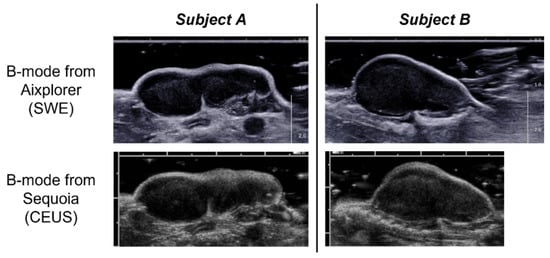

2.1. Experiment

2.3. SWE

2.4. CEUS